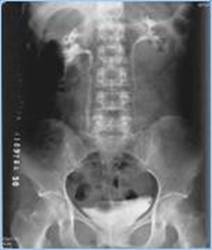

常规食管、十二指肠及小肠钡餐检查,钡剂灌肠检查,经内镜逆行胰胆管造影(Encoscopic Retrograde Cholangiopancreatography,ERCP)检查,T管及瘘管造影检查,静脉性肾盂造影(Intravenous Pyelography, IVP),泌尿系逆行造影,以及子宫输卵管造影等多种造影检查。